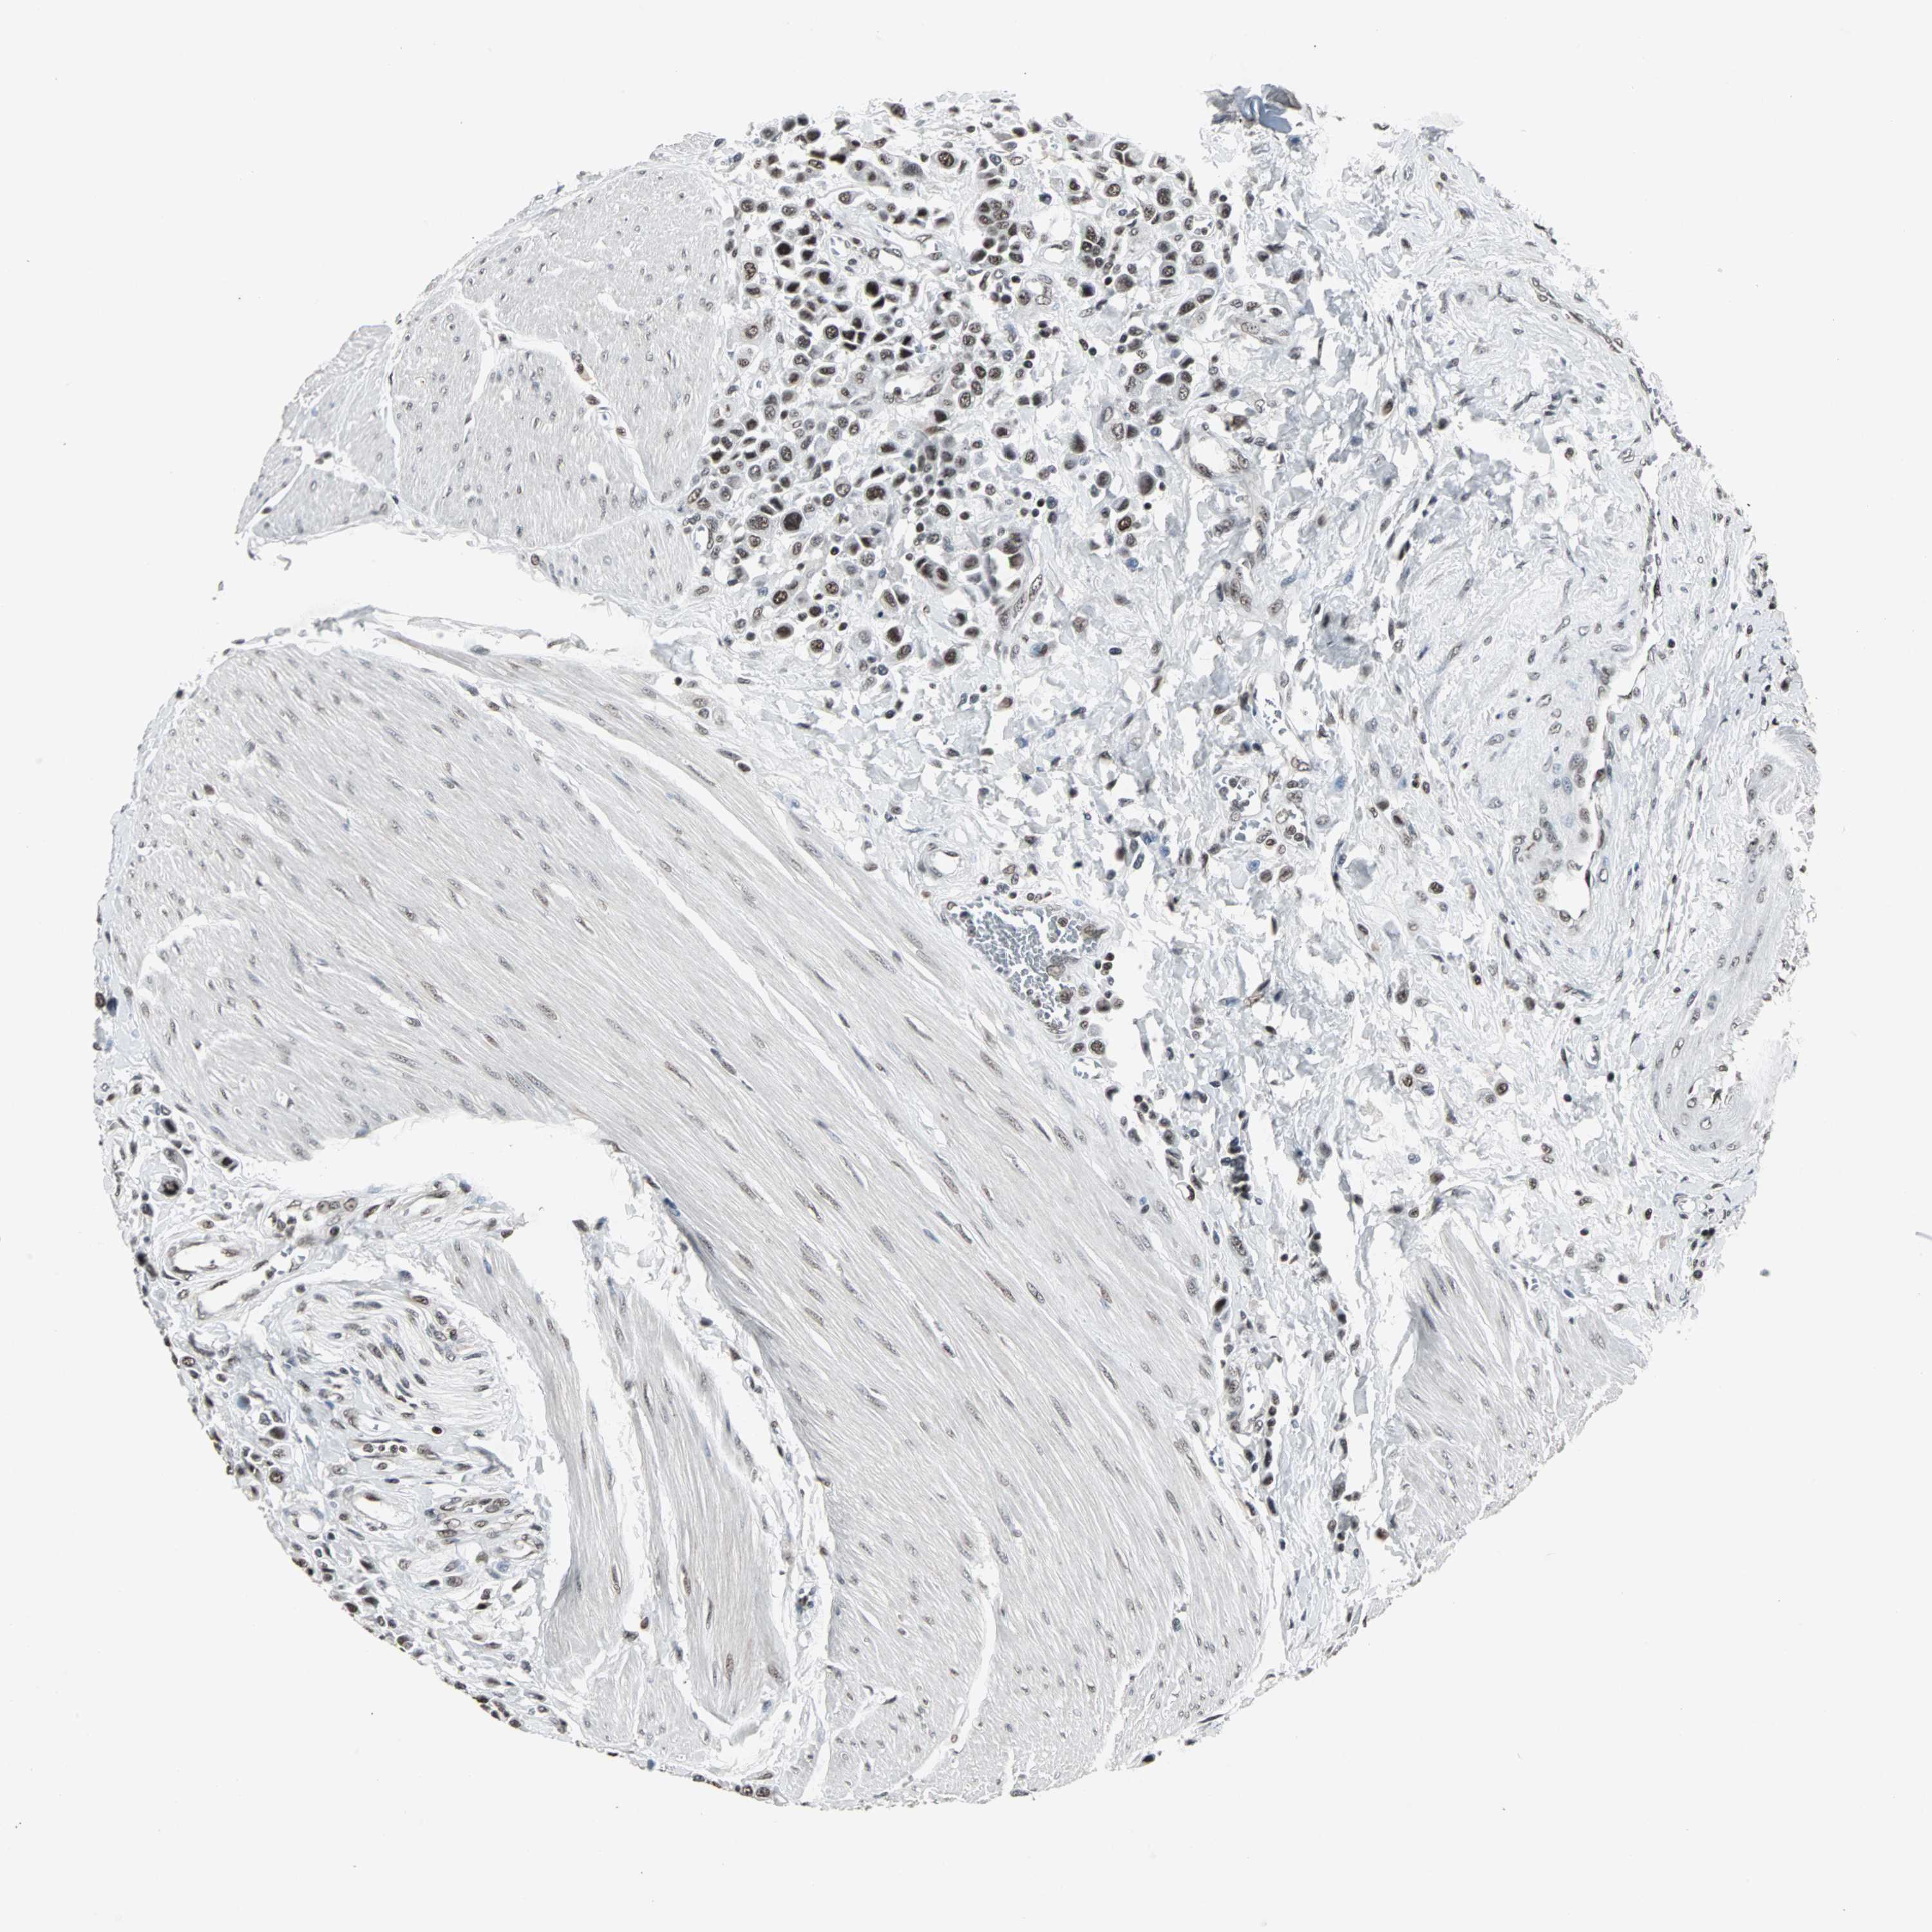

UROTHELIAL CANCER - Protein expressioni

A mouse-over function shows sample information and annotation data. Click on an image to view it in a full screen mode. Samples can be filtered based on level of antibody staining by selecting one or several of the following categories: high, medium, low and not detected. The assay and annotation is described here.

Note that samples used for immunohistochemistry by the Human Protein Atlas do not correspond to samples in the TCGA dataset.

Antibody stainingi

Antibody staining in the annotated cell types in the current human tissue is reported as not detected, low, medium, or high, based on conventional immunohistochemistry profiling in selected tissues. This score is based on the combination of the staining intensity and fraction of stained cells.

Each image is clickable and will lead to virtual microscopy that enables deeper exploration of all samples and also displays staining intensity scores, fraction scores and subcellular localization as well as patient and tissue information for each sample.

Antibody HPA006782

Staining

High

Medium

Low

Not detected

Intensity

Strong

Moderate

Weak

Negative

Quantity

>75%

75%-25%

<25%

None

Location

Nuclear

Cytoplasmic/membranous

Cytoplasmic/membranous,nuclear

Urothelial carcinoma, High grade

Urothelial carcinoma, Low grade